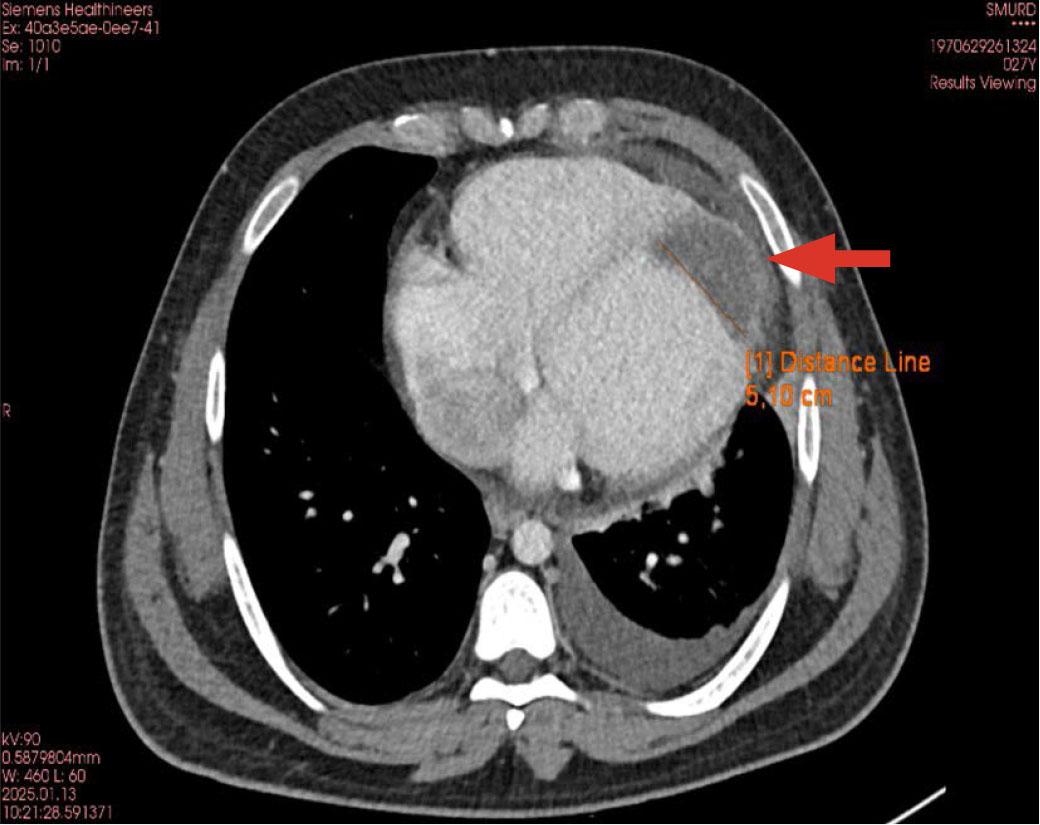

FIGURE 1.